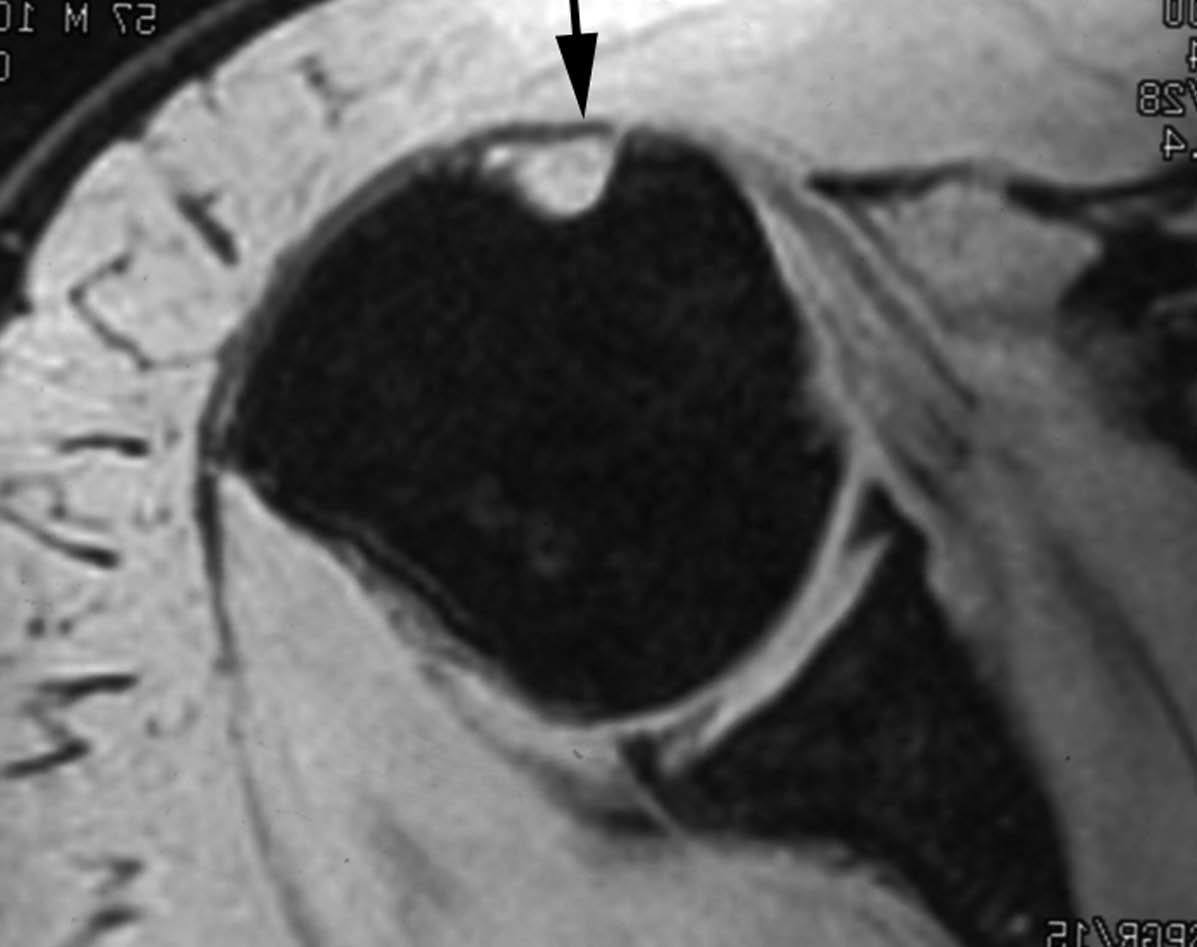

POLPSA (posterior labral periosteal sleeve avulsion)

Esta lesión se asemeja a la ALPSA, pero ocurre en el borde glenoideo posterior. El LG se halla desplazado hacia dentro y por detrás del borde glenoideo posterior. El mecanismo de producción del POLPSA es una dislocación posterior, y por tanto se puede encontrar también un Hill Sachs invertido19 (fig. 14).

. Artrorresonancia axial T1 con supresión grasa donde se observa una rotura del labio glenoideo posterior con desplazamiento posteromedial (flecha). Nótese la situación del labio glenoideo en comparación con una rotura sencilla, no desplazada, que se observa en la figura 13. Obsérvese la presencia de una lesión de Hill-Sachs invertida (cabezas de flecha), en relación con una dislocación posterior con reducción.Lesión de Bennett